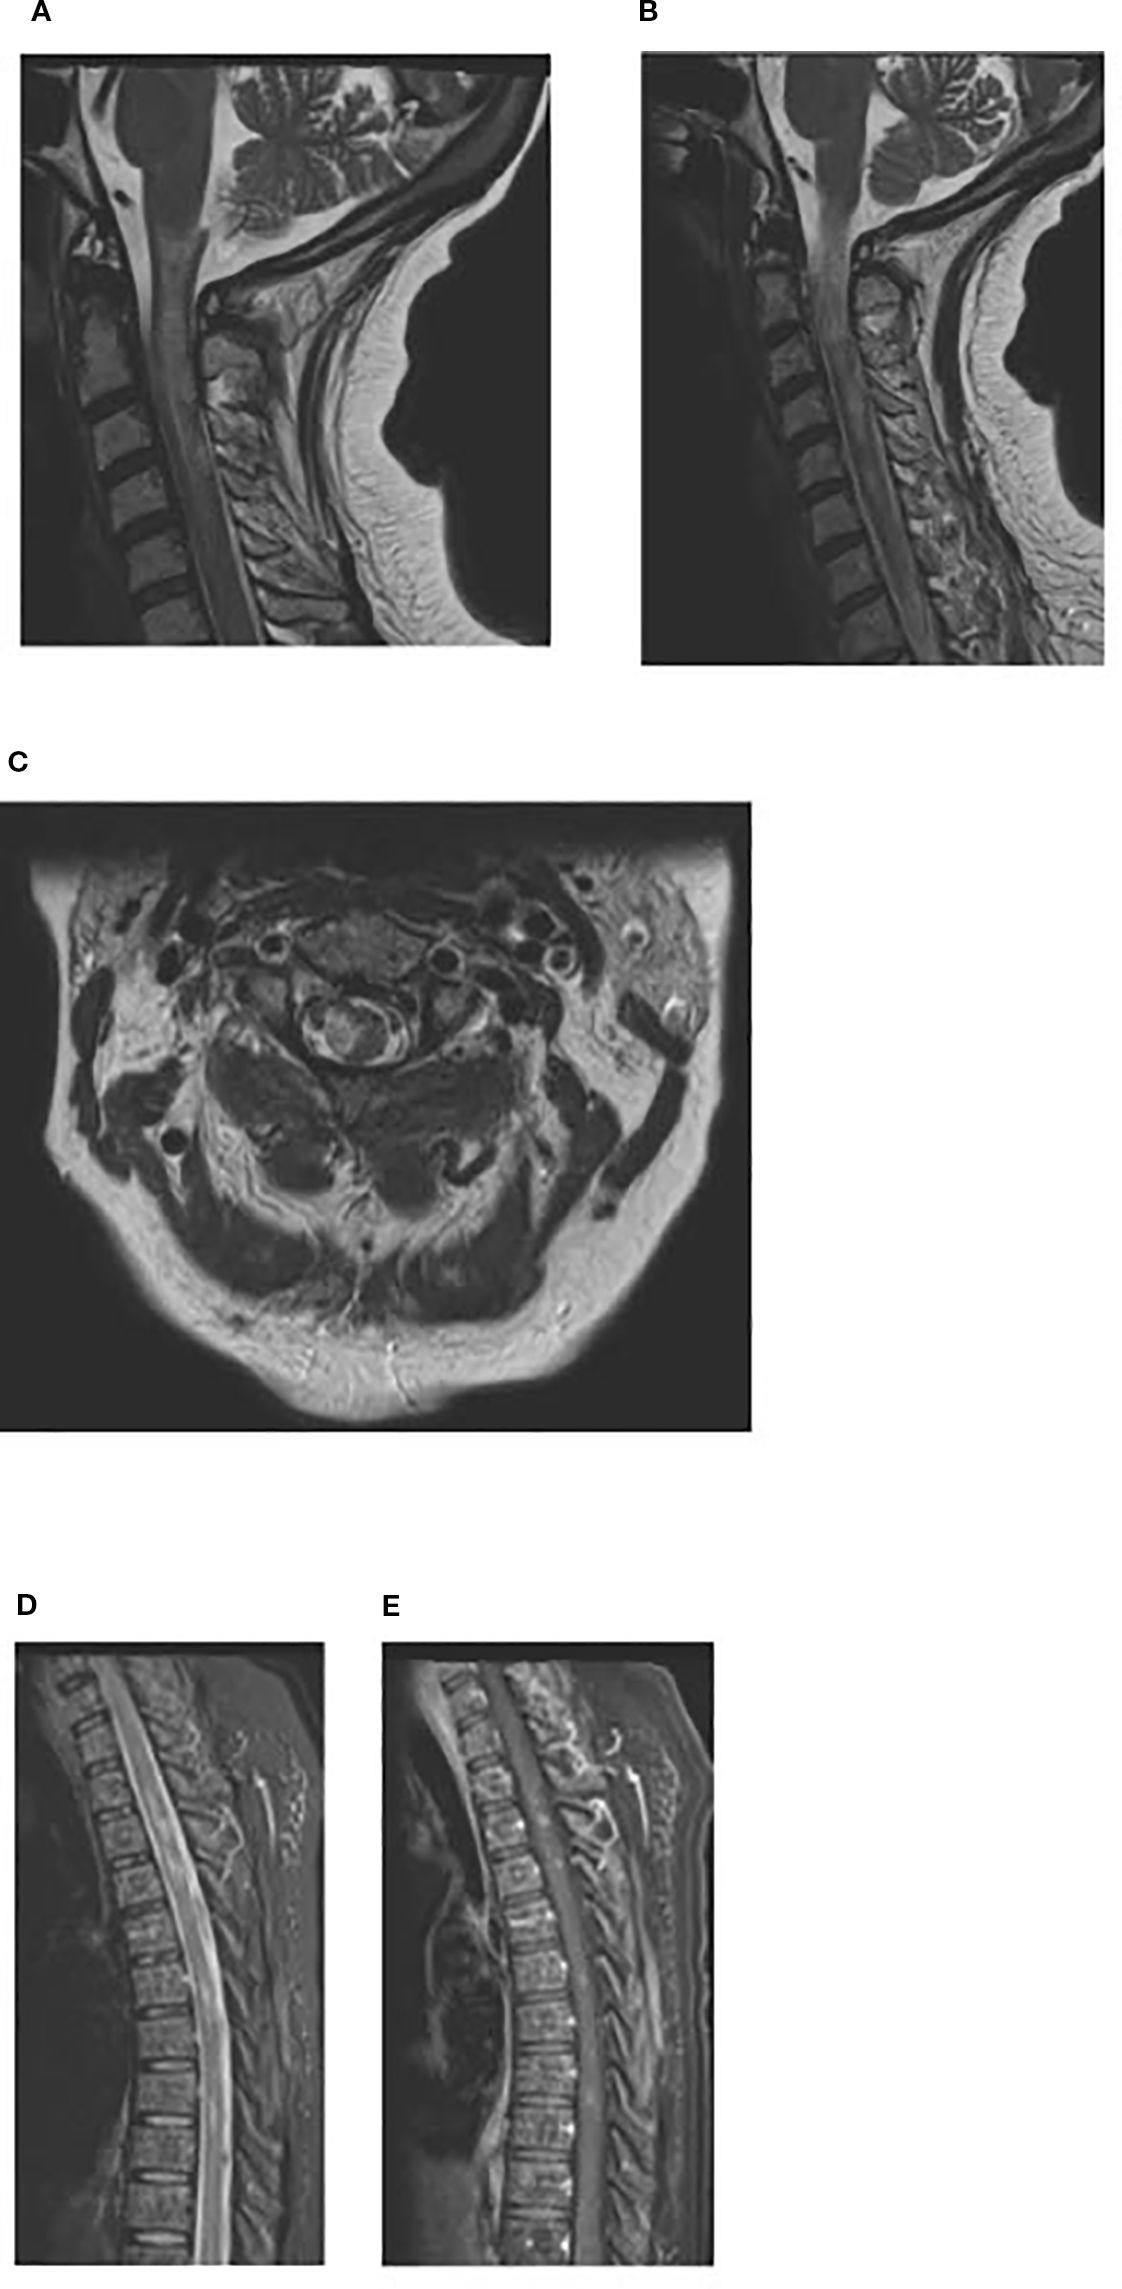

The patient underwent CAR-T cell collection and around a month later, the patient began lymphodepleting chemotherapy followed by CAR-T cell infusion. In mid-April 2024 (Day +0), the patient received CAR-T Axicabtagene ciloleucel. On day +2, the patient was febrile, tachycardic, and hypotensive and was determined to have CRS grade 2 and received standard treatment with Tociluzumab 8mg/kg/dose (600mg in IV 0.9 NaCl; dose 1 on day +3, 2 doses (560mg and 600mg) on day +4, and 1 doses on day +14), and steroids (IV dexamethasone 10mg for 13 days). The patient had clinical bilateral parotid enlargement; a CT of the neck and face on day +4 (Figure 4) showed symmetric enlargement of the parotid glands, with numerous, small hyperdense nodules and no evidence of abscess. The parotid swelling was watchfully observed, while continuing treatment for CRS and neurotoxicity. On day +5, the patient had confusion and speech abnormality; EEG showed bifrontally and midline predominant epileptiform discharges, and generalized slowing. MRI on day +5 showed mild paranasal sinus disease with mucous retention cyst or polyp in the left maxillary sinus. By Day +13, ICANS and CRS improved. Parotid swelling subsided. Steroids were tapered off over the next few days. On day +17, the patient was discharged. On day +38, the patient’s PET scan showed improvement of disease, with a Deauville score of 3 consistent with CR, and completely normal parotid glands. On day +364, the surveillance PET scan showed continued CR, indicating remission of DLBCL.

Figure 4. CT day +4: symmetric enlargement of the bilateral parotid glands, with numerous small hyperdense nodules.